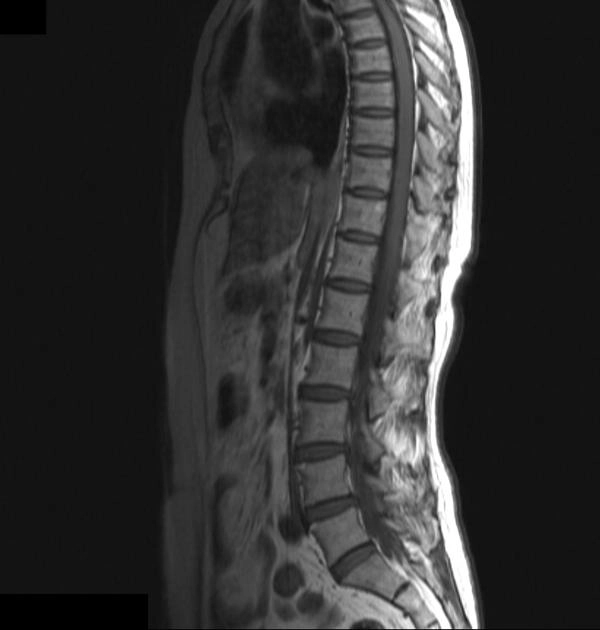

Dị dạng mạch máu cột sống (Spinal vascular malformations)

Rò động - tĩnh mạch màng cứng cột sống (Spinal Dural Arteriovenous Fistula - SDAVF)

Dị dạng động - tĩnh mạch tủy sống (Spinal Arteriovenous Malformation - AVM)

Dị dạng hang tủy sống (Spinal cord cavernous malformation)